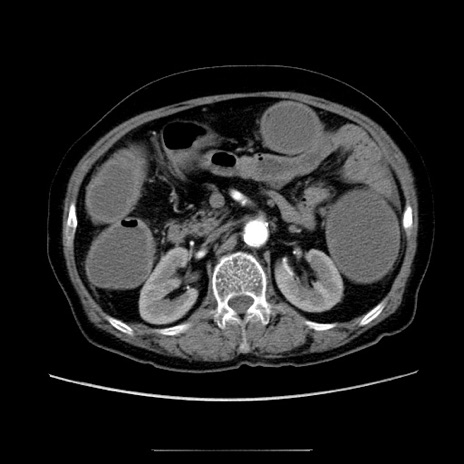

症例5(横断像)

【症例】70歳代女性

【主訴】お腹が張る

【現病歴】1週間くらい前から腹部膨満の自覚あり。昨日夜から増悪したため、本日救急外来受診。

【身体所見】意識清明、BT 36.5℃、BP 165/106mmHg、HR 80bpm、SpO2 98%、腹部:膨満、軟、自発痛・圧痛なし、触診にて不快感あり、腸蠕動音:減弱

【データ】WBC 12600、CRP 1.04